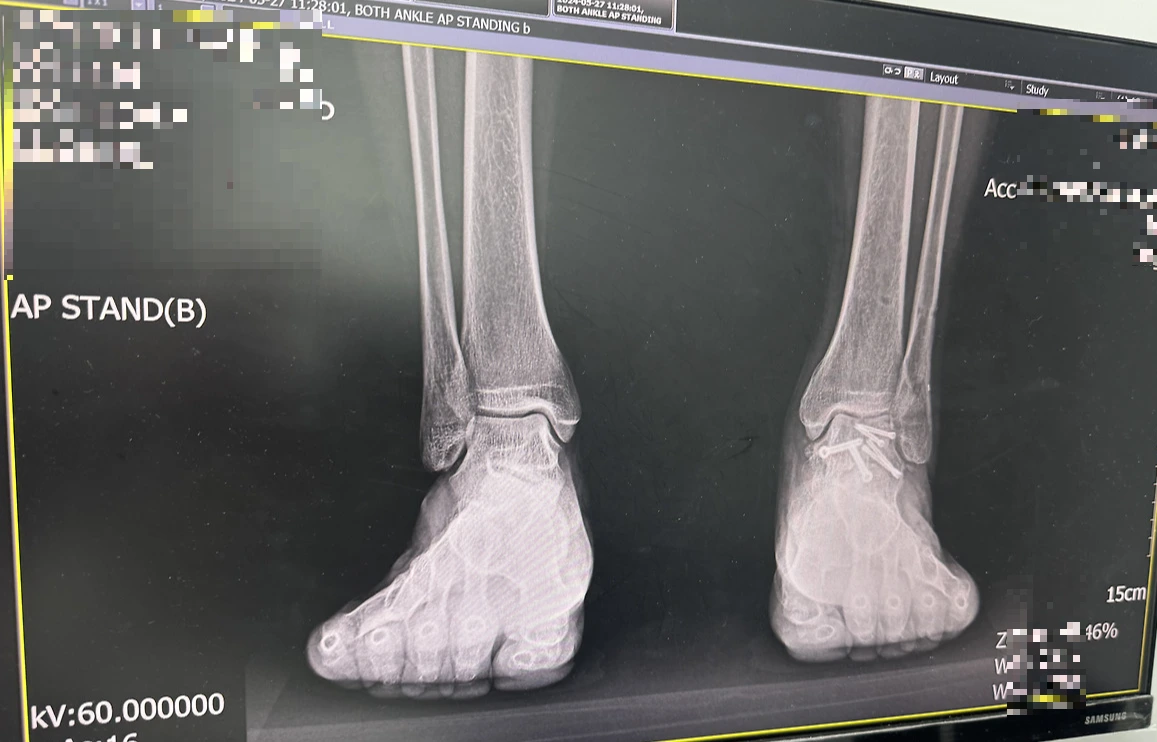

IMG_3233.HEIC 정강이 핀제거 후

당장 몇 달 앞으로 다가온 발목에 박힌 핀을 제거하는 수술이 걱정되었다. 수술을 하게 되면 또다시 발목을 고정해야 하기 때문에 발목이 굳고 근육이 빠지는 현상을 또 겪어야 하기 때문이다. 지금도 완전히 굳어있는 발목을 풀어놓지 못했는데, 이 상태에서 발목을 고정하고 굳어지면 상태가 더 악화될 것만 같았다. 이런 생각들로 불안이 증폭되기 시작했다. 그러나 그냥 걱정만 하고 있을 수는 없었다. 당장 다리 상태가 이전과 많이 다르게 느껴지고 조금 절뚝인다 해도 걸을 수는 있기 때문이다. 그러니 수술 전 발과 다리의 기능을 최대한 회복시켜 놓기로 마음먹었다.